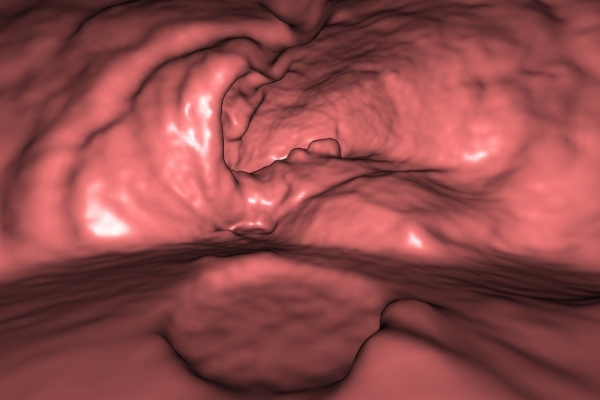

Detailbild MRT

Was ist der Unterschied zwischen einer MRT- und einer CT-Untersuchung?

Die MRT (Magnetresonanztomographie) arbeitet mit Magnetfeldern und Radiowellen und eignet sich besonders für Untersuchungen der Weichteile wie Gehirn, Muskeln oder Gelenke. Die CT (Computertomographie) nutzt Röntgenstrahlen und liefert schnelle, hochauflösende Bilder, insbesondere für Knochen, Lunge oder innere Organe. Die Wahl der jeweiligen Untersuchung richtet sich an das individuelle Krankheitsbild und wird bei der Überweisung festgelegt.